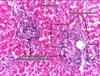

What type of tumour are these images? Describe why.

Squamous cell carcinoma

- Keratin at the top

- Intracellular bridges - parallel lines between cells

- Swirls of keratin